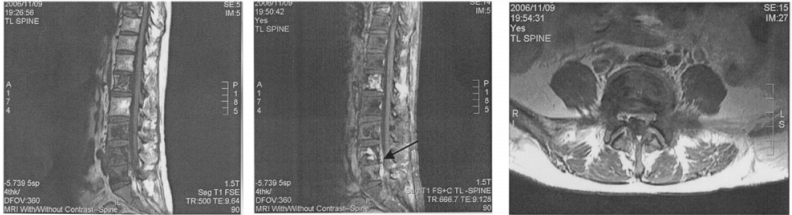

72 一位 48 歲女性,曾因肺癌及骨轉移接受化學及放射線治療,近日漸漸出現下肢酸麻及無力,接受顯影 劑注射前(左圖)及注射後(中圖及右圖)之磁振造影檢查。其腰椎除了明顯的 Bone metastasis 外,在 第四及第五腰椎部位(箭號所指處)有新的病變,下列何者為最正確的診斷並且能解釋其臨床症狀?

(A) Pathological compression fracture (B) Epidural metastasis (C) Infectious spondylitis (D) Post-irradiation myelitis